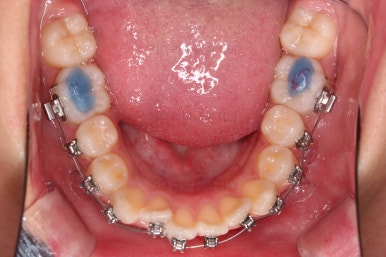

1. 초진 시 입안의 모습 평가

부산치아교정치과 키다리아저씨치과에 처음 내원했을 당시의 입 안의 모습입니다.

전반적으로 윗니가 나와있는 양상이고요.

앞니는 뻐드러져 있네요.

아래 앞니는 위로 솟구쳐 올라서 윗니 뒤쪽을 강하게 치고 있는 과개교합 양상이었고요.

위아래 앞니쪽이 삐뚤어져 있는 상태였습니다.

우선 윗니만 장치를 부착했습니다.

순서는 윗니 장치 부착 후 발치를 하고, 가지런하게 된 뒤에, 과개교합 개선을 위한 특별한 장치가 들어가면서 아랫니에도 브라켓을 부착하기로 정했습니다.

윗니가 가지런해진 뒤에는 부산치아교정치과 키다리아저씨치과에서는 ABP라고 하는 장치를 사용해 주면서 아랫니에도 브라켓을 부착합니다.

깊게 물리는 과개교합을 개선하기 위함인데요.